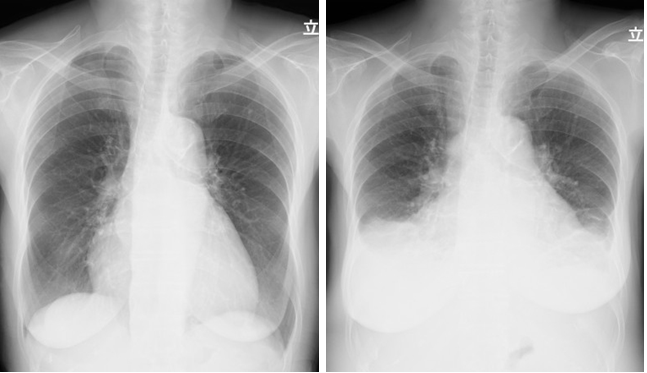

Examination revealed severe edema throughout the body, including the face and extremities. Atrial fibrillation (Af) and lower voltage findings were observed on the electrocardiogram (ECG) (Figure 1). SpO2 was 98-99%. Chest XP showed moderate pleural effusion in both lungs associated with bilateral vague cost-phrenic angles, which was much different from the previous X-P (Figures 2a, 2b). Based on the above, she was diagnosed with an acute exacerbation of chronic heart failure and was immediately hospitalized. The progress diagram of this example described above is shown in Figure 3, which revealed the changes in Hb values for recent years.

Figure 2 Comparison of the chest X-ray. 2a: unremarkable findings in stable period on May, 2020, 2b: bilateral pleural effusion in admission on Feb, 2021.